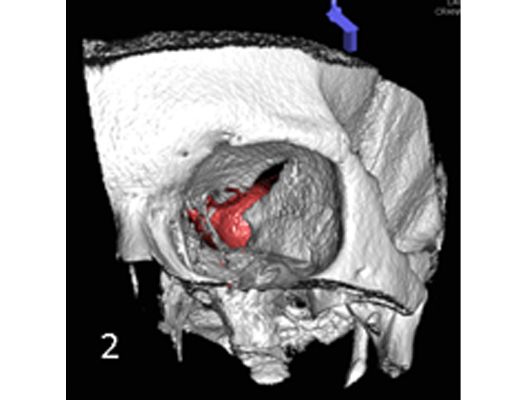

Mit den modernen Verfahren zur Wiedereröffnung von verschlossenen Blutgefäßen können wir Patienten mit Schlaganfall in vielen Fällen helfen. Das folgende Beispiel zeigt die angiographischen Bilder eines Patienten, der mit vollständiger Lähmung der rechten Körperhälfte und einer schweren Sprachstörung eingeliefert wurde. Ursächlich zeigte sich ein Verschluss der linken Halsschlagader, vermutlich auf dem Boden einer arteriosklerotischen Einengung (Bild 1). Das Gefäß wurde daraufhin mit einem Stent wiedereröffnet (Bild 2). Zusätzlich zeigte sich ein Verschluss der Endstrecke des Gefäßes durch Blutgerinnsel (Bild 3). Diese konnten vollständig entfernt werden (Bild 4). Der Patient erholte sich nach der Behandlung innerhalb weniger Tage vollständig.